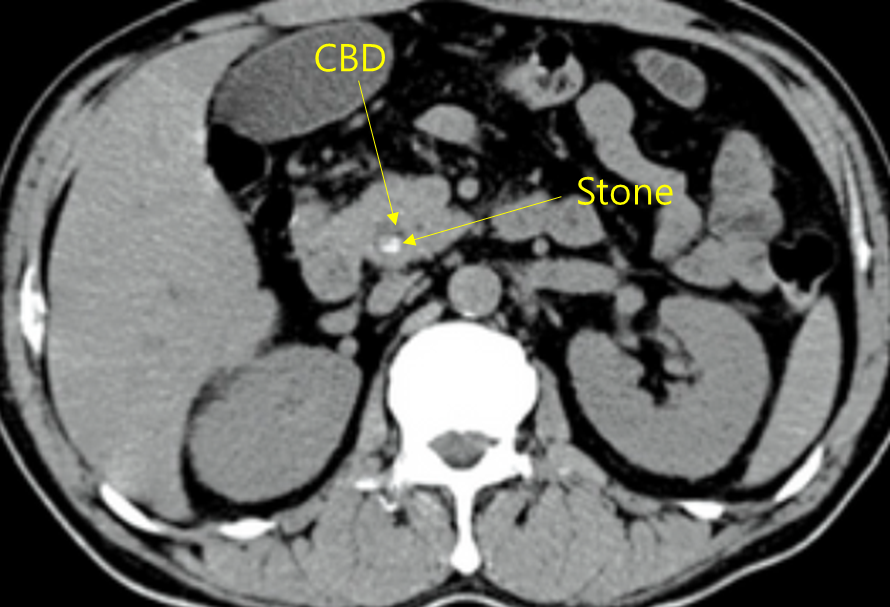

48세 여자가 어젯밤부터 오른쪽 윗배가 심하게 아프다며 병원에 왔다. 과식을 하면 종종 아팠다고 한다. 어제 저녁 회식을 하며 삼겹살을 많이 먹었다고 한다. 혈압 130/90mmHg, 맥박 100회/분, 호흡 20회/분, 체온 37.5℃이다. 급성 병색이고 공막에 황달이 있다. 오른쪽 윗배에 뚜렷한 압통이 있으며 반동압통은 없다. 혈액검사 결과는 다음과 같다. 복부 컴퓨터단층촬영 사진이다. 진단은?

백혈구 11,500/mm3, 혈색소 12.6g/dL, 혈소판 130,000/mm3, 총빌리루빈 6.4mg/dL, 알칼리인산분해효소 385U/L, 아스파르테이트아미노전달효소 102U/L, 알라닌아미노전달효소 97U/L

Img | CT: CBD stone |

오른쪽 윗배, 과식, 고지방식 후 악화되는 biliary colic pain이 있는 환자이며, 이와 더불어 황달, 발열이 있으므로 급성 담관염의 Charcot’s triad를 만족한다. 혈액검사에서도 총빌리루빈, ALP 증가 등 담즙 정체 소견이 확인된다. 급성 담관염의 원인은 대개 온쓸개관돌이나 온쓸개관암도 원인이 될 수 있다. 복부 CT에서 담관 내에 하얗게 보이는 온쓸개관돌이 확인되므로, 답을 고를 수 있다.